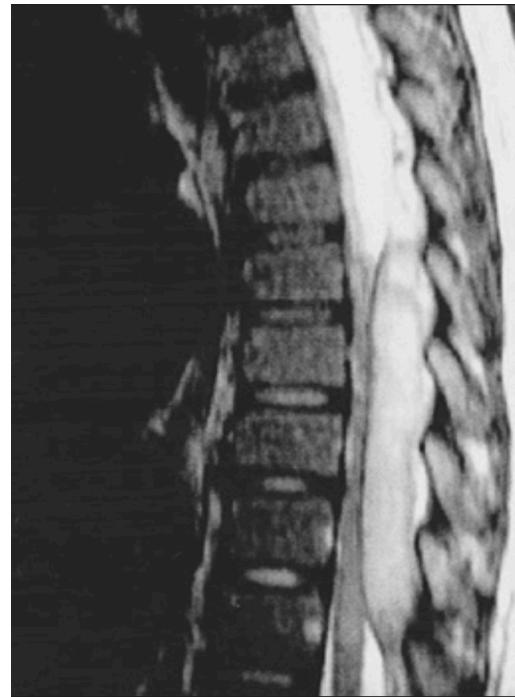

Cauda Equina Syndrome Z

- Etiology: Severe compression of nerve roots in the thecal sac of lumbar spine, most commonly due to acute lumbar disc herniation

- Critical: Early diagnosis is essential

Diagnosis:

- Urgent MRI to confirm cause

Treatment:

- Prompt surgical decompression

- Should be performed within 24 hours, absolutely within 48 hours